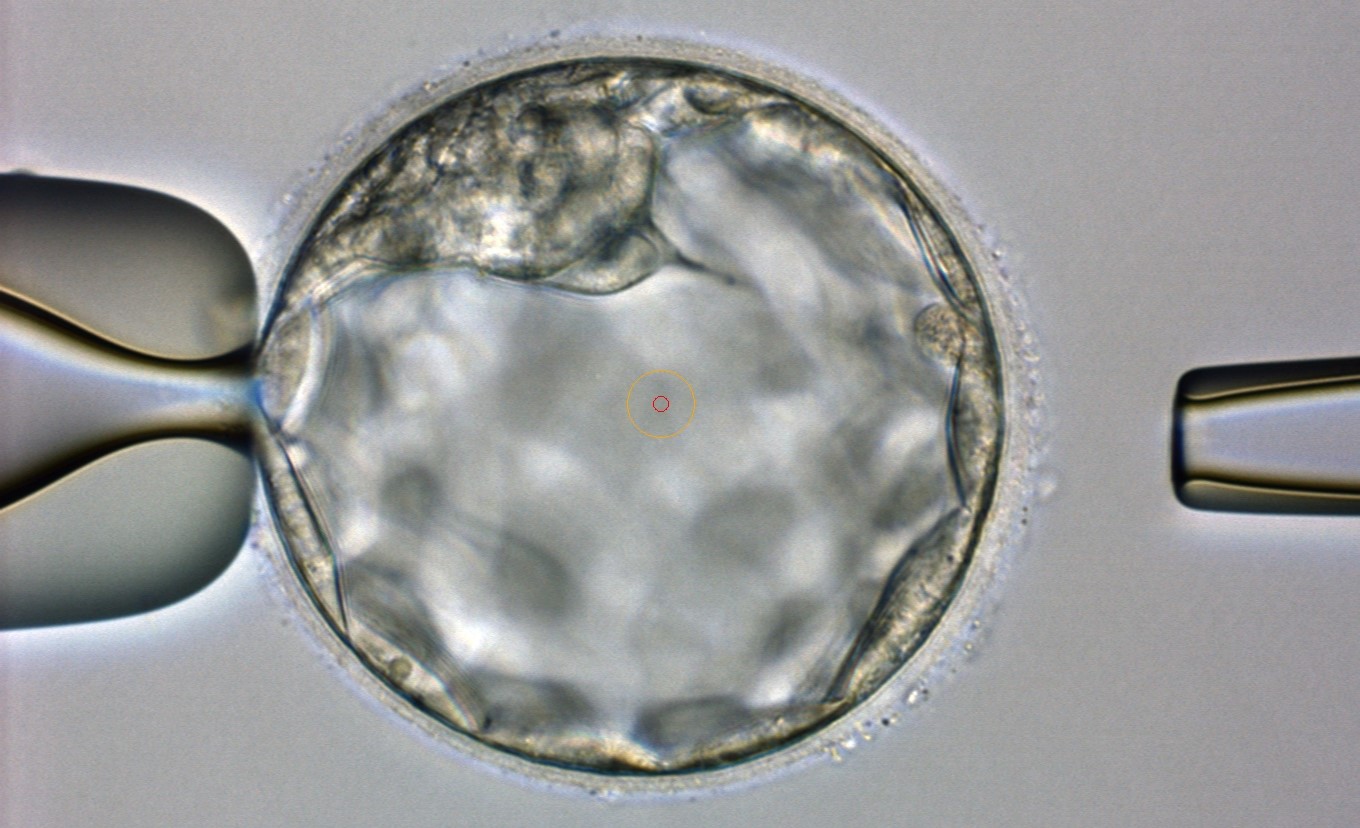

After follicle development is deemed acceptable, a simple injection, called the trigger shot, to induce final egg maturation will be utilized. We will then schedule the egg retrieval procedure. The remainder of the IVF process is similar to conventional IVF, where we then fertilize the eggs and sperm in the laboratory and create embryos.